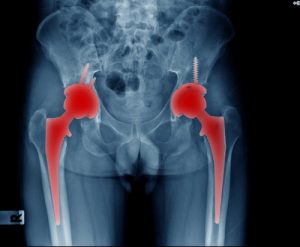

- Тотальное (полное) эндопротезирование. Проводится при поражении всего сустава и заключается в замене обоих компонентов: и головки, и суставной впадины. Это позволяет успешно восстановить его функциональность и вернуть пациенту возможность вернуться к полноценной активной жизни даже при запущенных формах артрита или артроза.

При планировании операций израильские хирурги-ортопеды применяют технологии 3D-моделирования, с помощью которых для каждого пациента им удается подобрать оптимальный вариант эндопротеза, который будет соответствовать анатомическим особенностям и сможет полноценно выполнять свои функции. В клинике Ихилов доступен широкий выбор конструкций из металла, керамики, пластика и других материалов, характеризующихся высокой прочностью, биоинертностью и долговечностью. Они могут фиксироваться цементным, бесцементным или комбинированным методом. Способ крепления эндопротезов также определяется индивидуально, в зависимости от материала, из которого они изготовлены и состояния кости.